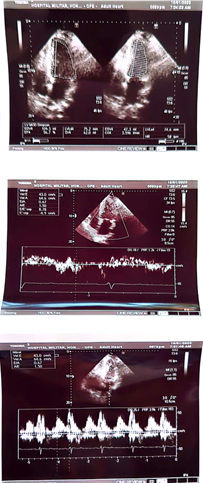

Case number 1: This is a 60-year-old male patient with a history of known hypertension for 10 years controlled with Candesartan plus hydrochlorothiazide 32/25 mg daily. Mixed dyslipidemia controlled with statin type atorvastatin 40 mg daily. Significant central obesity BMI of 35. Also, sedentary life. History of 4 inoculations with the Pfizer vaccine, he began to present with acute respiratory distress, palpitations, paroxysmal nocturnal dyspnea, orthopnea, saturation of 85% by oximetry. On physical examination: marked arterial hypotension 80/60 FC: 135 beats per minute Respiratory rate of 28 per minute acrocyanosis and on cardiac auscultation: rhythm Irregularly irregular with a more audible mitral regurgitation murmur at the apex of the heart radiating to the axilla. Lung auscultation: crackles from the middle third to the base of both lung fields. The electrocardiogram shows rapid atrial fibrillation rhythm at 135 beats per minute. Chest X-ray: Grade III-IV cardiomegaly with acute pulmonary edema. An echocardiogram was performed, showing findings compatible with dilated cardiomyopathy with left ventricular ejection fraction of 10%. Global hypokinesia, in doppler moderate-severe mitral regurgitation. Moderate-severe tricuspid regurgitation with pulmonary systolic pressure of 90 mmHg. Tissue Dopplar significant increase in left intraatrial pressure 25. In addition, the following laboratory analyzes were performed: Complete blood count: leukopenia: 2,000 leucocytes. Hb: 12.5 g/dl. Thrombocytopenia: 107,000 platelets, severe eosinopenia and lymphopenia. Elevated D-dimer 2.0 (normal value up to 0.50) Elevated NtproBNP 3,500 (normal up to 300). C-reactive protein of 32 Normal up to 10. Ferritin of 750 (normal up to 250). Creatinine: 3.2 mg/dl Urea: 70, TGO: 110, TGP:115.

Echocardiogram

1. Findings compatible with dilated cardiomyopathy secondary to graphene hydroxide

2. Severely depressed ejection fraction (10%).

3. Moderate-severe mitral regurgitation

4. Elevated left intraatrial pressure (20)

5. Ventricular filling pattern of a restrictive nature

6. Moderate pulmonary arterial hypertension

7. Fast Atrial Fibrillation Rhythm.

Control echocardiogram is performed

We can appreciate the amazing size left ventricle and normal global and segmental contractility with normal left ventricular ejection fraction (75%). Previous 10%. In addition, the patient was asymptomatic from the cardiological point of view. In such a way that all the medication that was started for the treatment of dilated cardiomyopathy was suspended, such as: Sacubitril/valsartan, furosemide, aldactone, ivrabadine, metoprolol, oral anticoagulants. The only treatment for her arterial hypertension was left with candesartan 16 mg per day and rosuvastatin 40 mg at night for mixed dyslipidemia. The following 6 patients 5 are male with ages: 28, 33, 35, 85 and one female: 95 years of age whose ejection fractions were similar 18, 17, 16 and 15% respectively and their evolution is similar to that of First case with an echocardiographic and clinical evolution to total normality. All patients currently lead a completely normal life.1-3